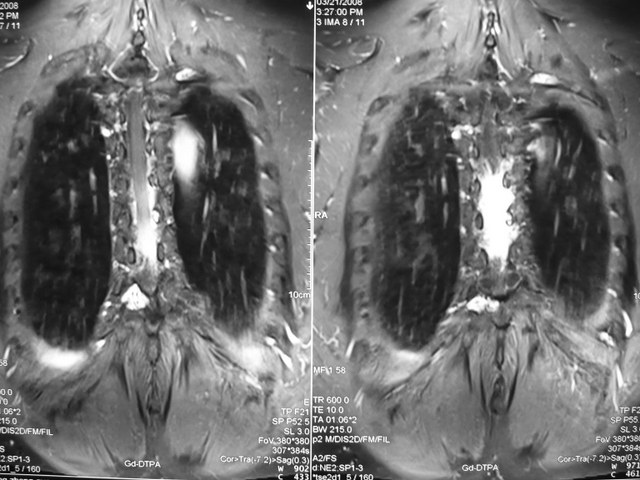

罕见血管脂肪瘤